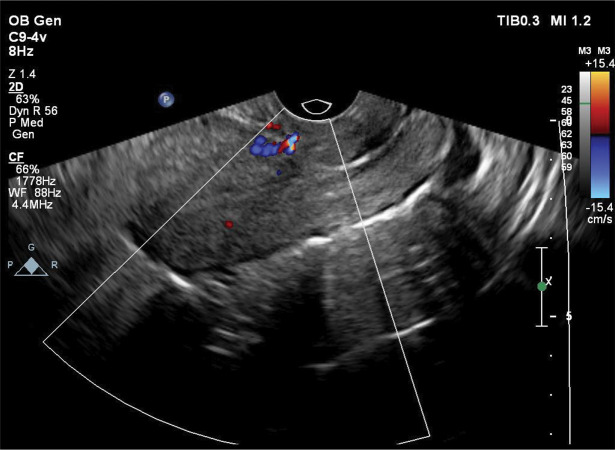

子宫动静脉畸形(AVM)是一种罕见但可能危及生命的疾病,其特征是阴道出血。诊断可以通过各种成像方式建立,包括多普勒超声,磁共振成像(MRI),计算机断层扫描(CT),或盆腔血管造影。治疗的选择受几个因素的影响,包括患者的年龄、临床症状、生育愿望、畸形的大小和解剖位置。对于育龄期希望保留生育能力的有症状的AVM患者,子宫动脉栓塞(UAE)被认为是首选的治疗方法。本文是关于子宫动脉栓塞失败后难治性阴道出血的处理。本报告提出一个病例子宫AVM在一个32岁的女性谁经历了异常阴道出血后人工流产。经多普勒超声证实子宫AVM的诊断。虽然进行了双侧UAE,但患者仍有明显的阴道出血。栓塞手术失败后,通过双侧腹下动脉结扎对患者进行了有效的治疗。阴道异常出血可能提示子宫动静脉畸形,特别是有剖宫产、人工流产或宫内扩张刮除(D/C)手术史的患者。虽然经导管UAE通常是一种有效的治疗方法,但它可能不是在所有情况下都成功。

Uterine arteriovenous malformation (AVM) is an uncommon yet potentially life-threatening condition characterized by significant vaginal hemorrhage. Diagnosis can be established through various imaging modalities, including doppler ultrasound, magnetic resonance imaging (MRI), computed tomography (CT), or pelvic angiography. The choice of treatment is influenced by several factors, including the patient's age, clinical symptoms, reproductive aspirations, and the size and anatomical location of the malformation. For symptomatic AVM in patients of reproductive age who wish to preserve fertility, uterine artery embolization (UAE) is considered the preferred therapeutic approach. This article is about the management of resistant vaginal bleeding after unsuccessful uterine artery embolization. This report presents a case of uterine AVM in a 32-year-old female who experienced abnormal vaginal bleeding following an induced abortion. The diagnosis of uterine AVM was confirmed via doppler ultrasonography. Although bilateral UAE was performed, the patient continued to experience significant vaginal bleeding. Following the unsuccessful embolization procedure, the patient was effectively managed through bilateral hypogastric artery ligation. Abnormal vaginal bleeding may be indicative of uterine AVM, particularly in individuals with a history of cesarean delivery, induced abortion, or dilation and curettage (D/C) procedures. While transcatheter UAE is generally an effective treatment, it may not succeed in all cases.